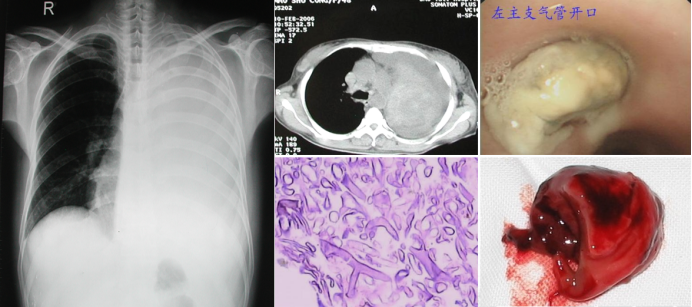

病例6:男性,21岁。主因“间断咳嗽、发热3个月”来我院治疗,伴间断右侧胸痛、夜间盗汗等。既往诊断1型糖尿病2年,血糖控制不佳,糖尿病酮症酸中毒,无外伤手术史,无烟酒嗜好。无家族疾病史。体格检查:一般好,双肺呼吸音清,右中肺野呼吸音稍低,未闻及干湿啰音。双下肢无水肿。T-SPOT-TB、G、GM试验均阴性;痰涂片、痰培养、BALF涂片培养均阴性。胸部CT显示肺部感染,右肺中叶实变;腹腔CT则可见坏死征象(图6)。支气管镜下观察到真菌生长形成新生物(图7),结合临床经验初步判断可能为毛霉感染。随后通过支气管镜介入技术取出该新生物(图8)。过程中引发出血,经抢救患者脱离危险。1周后复查CT,患者在未接受任何全身抗真菌治疗情况下,病灶缩小(图9)。需要注意的是,此类操作具有较大风险。

图片

6  病例6治疗前胸腹部CT